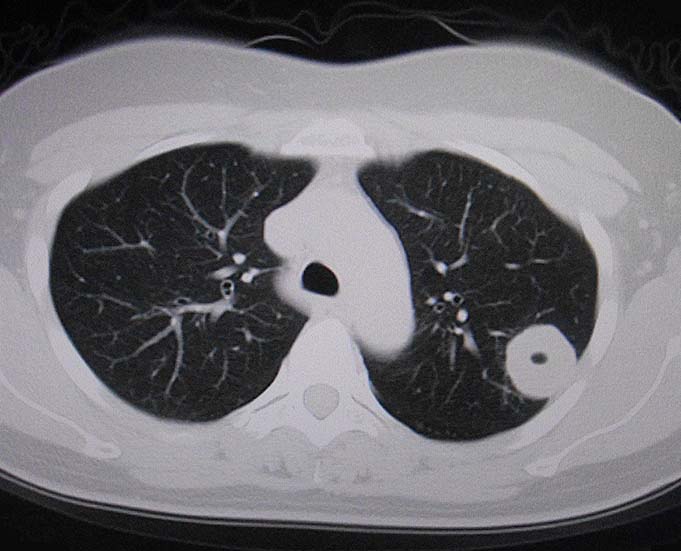

健診により左上葉S1+2に32mmの腫瘤を指摘される. 症状なし. 肺癌を疑われ, 気管支鏡検査を行われるが診断がつかず切除生検が施行された.